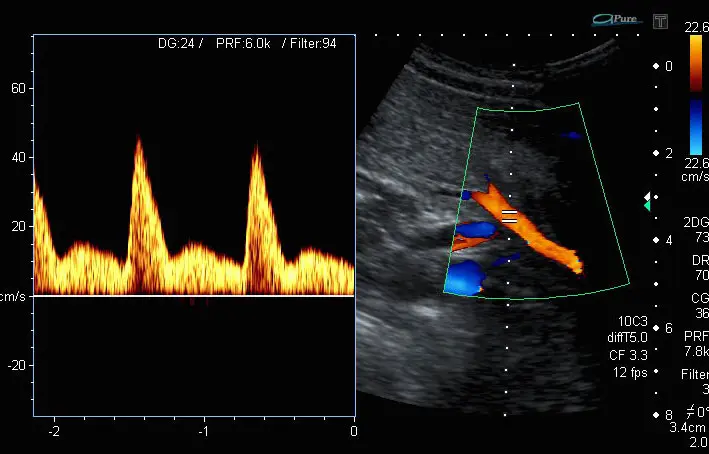

Um den Blutfluss in der Arteria uterina zu beurteilen, wird eine spezielle Ultraschalluntersuchung namens Farbdopplersonographie durchgeführt. Diese Untersuchung ermöglicht es, die Blutflussgeschwindigkeit und -richtung in den Gefäßen zu visualisieren.

Die Farbdopplersonographie wird in der Regel ab der 1Schwangerschaftswoche durchgeführt. Sie liefert wichtige Informationen über:

- Die Versorgung des Babys mit Sauerstoff und Nährstoffen: Ein erhöhter Widerstand im Blutfluss der Arteria uterina kann auf eine unzureichende Versorgung des Babys hindeuten.

- Mögliche Schwangerschaftskomplikationen: Veränderungen im Blutfluss der Arteria uterina können ein Hinweis auf Präeklampsie, Hypertonie oder andere Schwangerschaftskomplikationen sein.

PI-Wert: Ein Maß für den Blutflusswiderstand

Ein wichtiger Parameter, der bei der Farbdopplersonographie gemessen wird, ist der Pulsatilitätsindex (PI). Der PI-Wert gibt Aufschluss über den durchschnittlichen Blutflusswiderstand in den Gefäßen. Ein erhöhter PI-Wert kann auf einen erhöhten Widerstand im Blutfluss hindeuten, was wiederum ein Zeichen für eine unzureichende Versorgung des Babys sein kann.